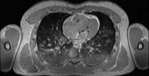

Visible Human male: Sectio transversalis 1453

CT

NMR

Pd                          / T2 \                         T1